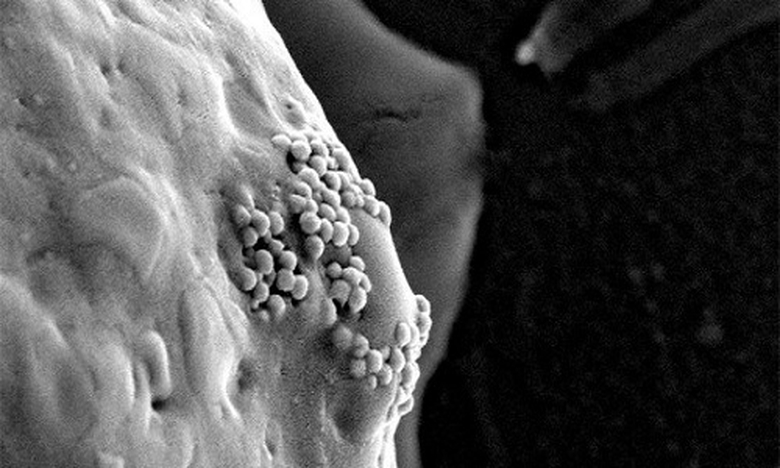

| Các hạt nano vàng bám trên bề mặt tế bào ung thư (Ảnh: D. S. Wagner) |

Những hạt nano vàng có xu hướng thấm qua các lỗ mạch và tập trung xung quanh khối u khi chúng được tiêm vào mạch máu cơ thể người bệnh. Khi các tế bào ung thư phát triển chúng sẽ bao phủ các hạt nano vàng này. Sau khi lọt vào bên trong tế bào ung thư, các hạt nano này sẽ được nung nóng bằng tia laser hồng ngoại hoặc sóng điện từ và đốt cháy các tế bào ung thư, tiêu diệt chúng.